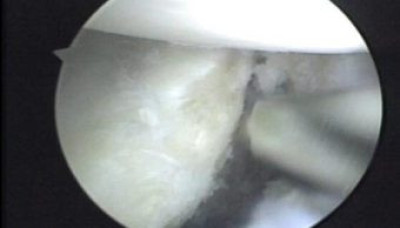

Con el uso de un palpador metálico se comprueba la estabilidad del reparo y la seguridad de los nudos